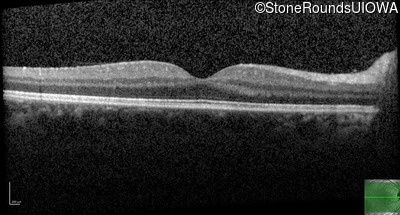

Optical Coherence Tomography - Right - 20/25

Exemplar / OCT Stack